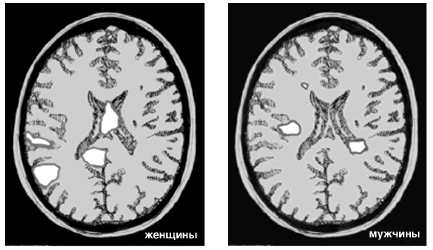

Приведенные ниже результаты сканирования мозга иллюстрируют исследование, проведенное доктором Браун. Они показывают, в каком участке мозга «располагается» любовь и почему мужчины и женщины относятся к этому чувству по-разному. Это снимки мозга мужчин и женщин, которые смотрят на фотографии людей, в которых они страстно влюблены.

Образы любви. Мужчины и женщины смотрят на фотографии любимых людей.

Белым цветом показаны активные области

Вы видите, что у мужчин светлых участков меньше, чем у женщин. Однако, когда эти снимки показываются в цвете, становится ясно, что активизированные участки мужского мозга действуют более интенсивно. Обширные активизированные участки женского мозга гораздо менее активны. У женщин таких участков больше, и расположены они не там, где у мужчин. Это объясняет, почему мужчины и женщины относятся к любовным отношениям по-разному.